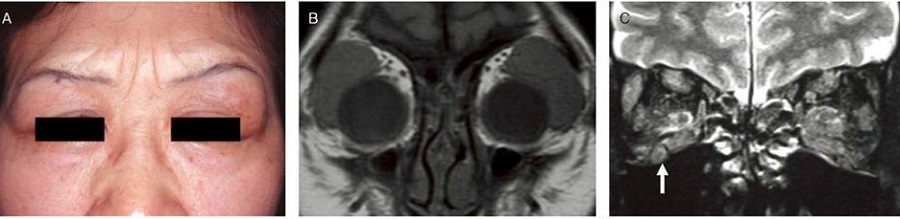

写真A:両側涙腺の対称的な腫大 B:MRI T1 強調画像(冠状断)で両側涙腺の対称性腫大 C:MRI T2 強調画像(冠状断)で両側涙腺の腫大・外眼筋腫大・眼窩下神経(三叉神経)の腫大(Jpn J Ophthalmol 59:1-7, 2015)

IgG4関連眼症は、甲状腺眼症・バセドウ病眼症と同じく、上眼瞼炎、外眼筋炎、眼窩内脂肪織炎、涙腺腫大を認めます(炎症部位がほぼ同じ)。(第55回 日本甲状腺学会 P2-07-04 橋本病と木村病に外眼筋腫大と眼瞼腫脹を合併し高IgG4 血症を呈した一例)[J Endocrinol Invest. 2014 Dec;37(12):1233-5.][BMC Ophthalmol. 2018 Jan 12;18(1):5.]

単純CTで、それら病変を評価するのは難しく、MRIがはるかに優れています。ただ、単純CTではミクリッツ病(Mikulicz病)の涙腺腫大が明瞭に写ります。

甲状腺眼症・バセドウ病眼症と思っていても、涙腺腫大・涙腺炎・涙嚢炎が見つかればIgG4関連眼症の鑑別を考える必要があります。[BMC Ophthalmol. 2018 Jan 12;18(1):5.]

IgG4関連眼症のMRI所見は、T2強調画像で涙腺炎に加え、

- 視神経周囲組織の炎症(IgG4 眼症は視神経炎を伴う場合がある)

- 様々な眼組織に腫瘤(眼球裏面に索状の腫瘤など)

- 三叉神経(眼窩上神経と眼窩下神経)の腫大[Ophthalmic Plast Reconstr Surg. 2019 Mar/Apr;35(2):170-176.]

を認める点が、甲状腺眼症・バセドウ病眼症と異なります。造影MRIでは、いずれも増強されます。